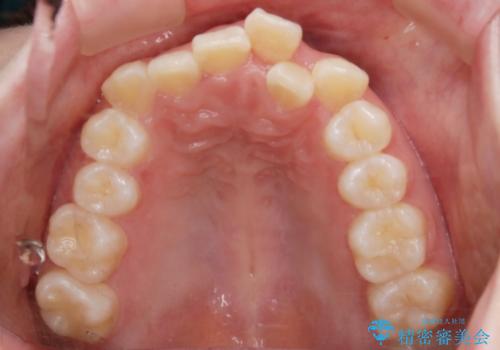

ハーフリンガル装置

ワイヤー矯正の中でも、上顎を裏側・下顎を表側に装置をつけて動かす方法をハーフリンガルといいます。

ハーフリンガルを選択すると、ワイヤー矯正の利点である抜歯ケースへの対応が可能な点と、表側の装置の欠点である装置が目立つという点をカバーして矯正治療を進めることができます。

表側の装置と違い、使えるワイヤーの種類に制限があり平均治療期間が長くなりやすい点、装置の作製自体の金額が掛かることから費用面で表側装置よりも高額になるという点はマイナスポイントであるといえますが、しっかりと口元を下げたり、噛み合わせの構築を行うことは遜色なく行えるため人気のある装置となっております。